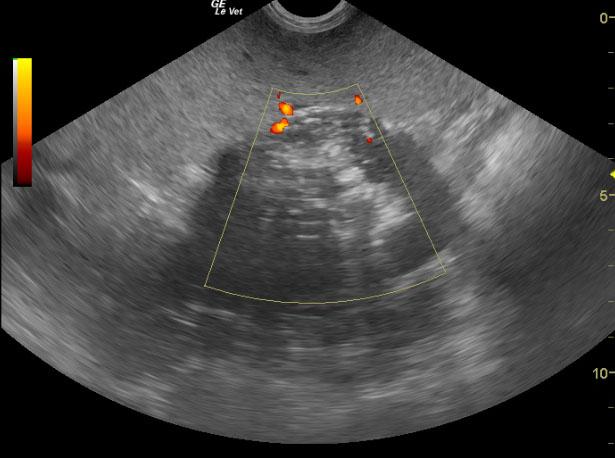

The pancreas was largely normal with minor age related changes in the right limb and right pancreatic base. However, the left pancreatic base opened up into a large 10+ cm mineralizing mass. This is consistent with pancreatic carcinoma. Some omental adhesions were noted in the mid-abdomen. The mesenteric root was not visualized given that it was obscured by the mass.